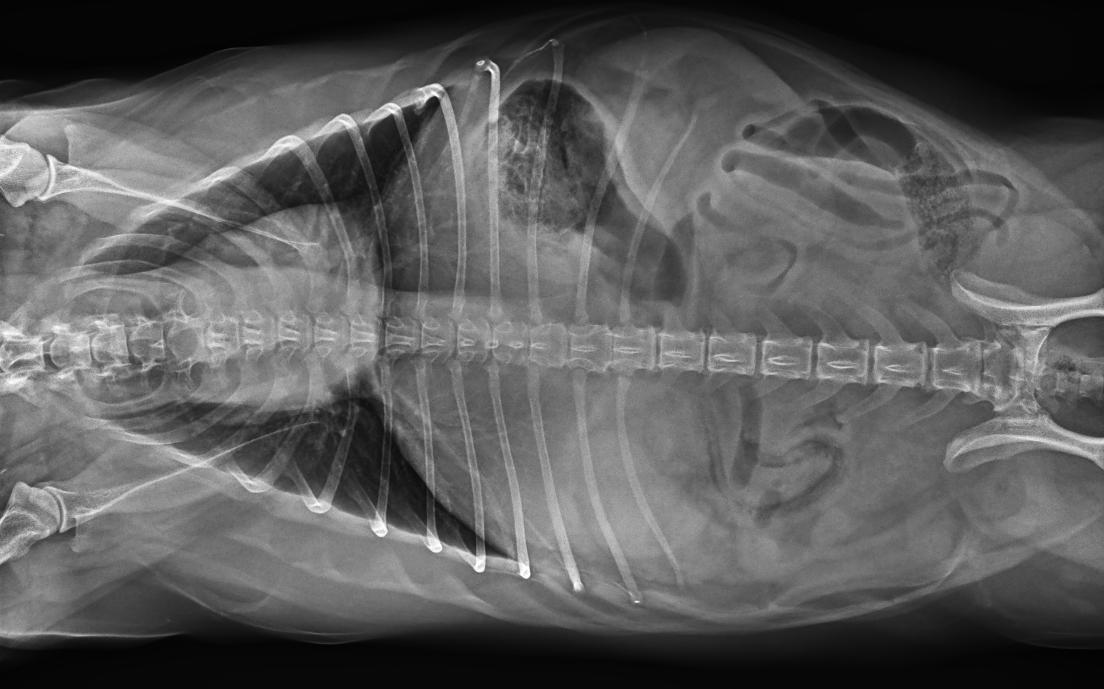

● 17*17大尺寸平板探測(cè)器,獲得高質(zhì)量圖像

● 優(yōu)異的空間分辨率及信噪比,提升圖像質(zhì)量

● 采用線噪聲消除技術(shù),使成像質(zhì)量提升40%

● 智能高效的圖像處理軟件,大幅提升圖像質(zhì)量

● 可浮動(dòng)床面設(shè)計(jì),滿足大部分中小型寵物檢查